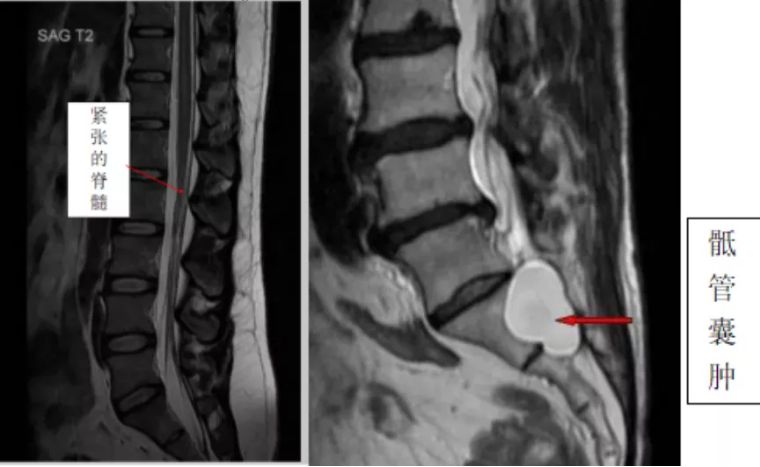

娄永利主任详细了解病情后,建议孟阿姨做一个腰骶部磁共振成像,结果显示,孟阿姨患有骶管囊肿。

骶管囊肿造成了脊髓的紧张,

从而引起孟阿姨的一系列症状。

这种脊髓紧张引起的一系列临床症状

称为脊髓栓系综合征